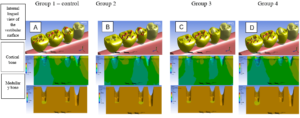

The treatment plan consisted of performing a total superior prosthesis obturator by the cloning technique and the preparation of a conventional removable partial prosthesis (PPR). Cloning of the total superior obturator prosthesis began with the application of solid vaseline on the bench and in the old prosthesis, the condensation silicone (Clonage®, Nova DFL, Brazil) was manipulated to model the inner part of the prosthesis, covering a portion of the outer edge, leaving it expulsive (figure 3).

Thus, because the patient already makes use of a shutter prosthesis, it is possible to choose to perform the cloning technique (DA CUNHA DINIZ et al., 2015), even though it was without adequate retention because it had passed the useful life of 3 years (ANTUNES et al., 2008), it was correctly constructed and restored adequate functional space. According to Gomes and Castro (2009) the technique consists in the realization of the silicone matrix, and the inclusion in muffle and for the duplication of teeth recommend fluid silicone, as it will prevent the formation of bubbles and irregularities. In this case, the technique underwent some modifications made by the authors to ensure greater agility to the procedure. The material of choice to obtain the replica of the base was the acrylic resin duralay, because it presents little polymerization contraction. As for the tooth region, it was made with wax 7, where in the next phase the teeth copied in wax were replaced by the stock teeth directly. The modifications showed a good cost-benefit ratio, not requiring the laboratory stage of acrylization in a conventional oven or microwave for the preparation of the clone.

To perform the final stage of the prosthesis a very relevant factor is acrylization. Wu & Schaaf (1989) showed that hollow shutter acrylization decreases weight from 33.06 to 6.55%, depending on the size of the defect. The literature indicates that lighter prostheses provide favorable retention and stability. Among its advantages is in the aid of swallowing, improvement in retention, preventing the overtaking of food and liquids through the maxillary defect. Factors that were fundamental for the choice of acrylization of the prosthesis in evidence.